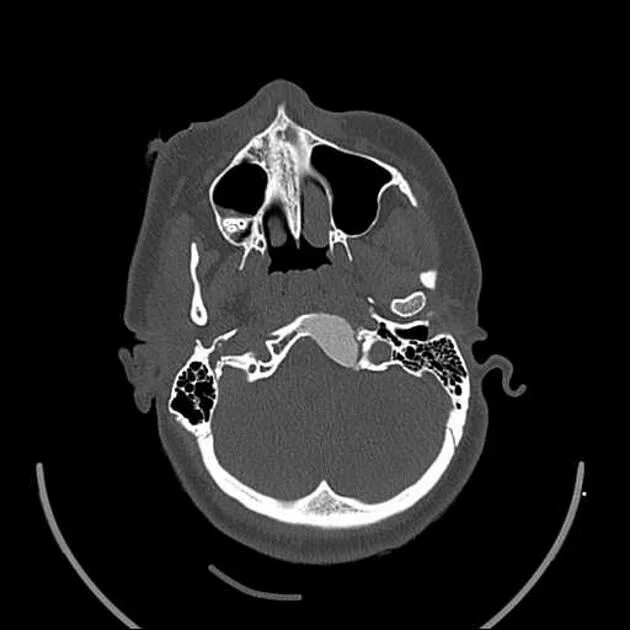

Череп на кт